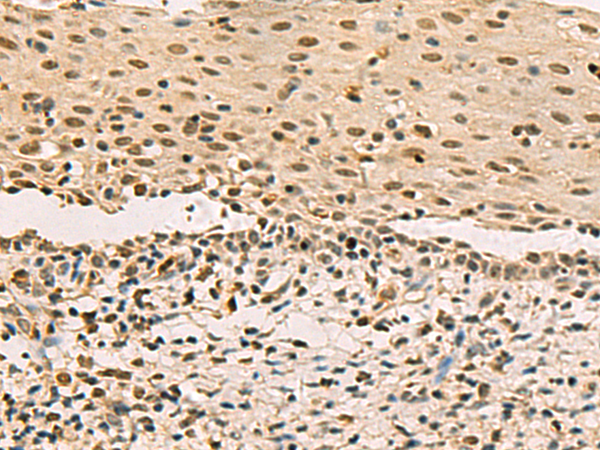

IHC positive control: |

Human cervical cancer |